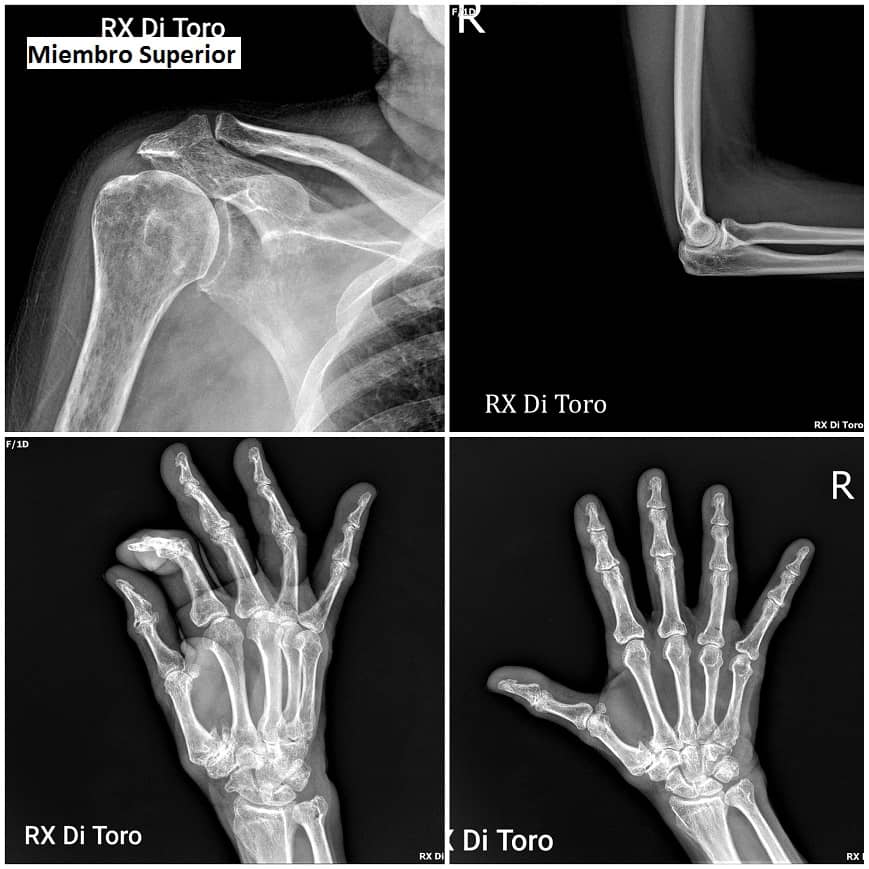

Utilizamos sensores Flat Panel, que nos permiten acortar al Máximo el tiempo de exposición (Dosis de Radiación) y obtener la adquisición inmediata de las imágenes.